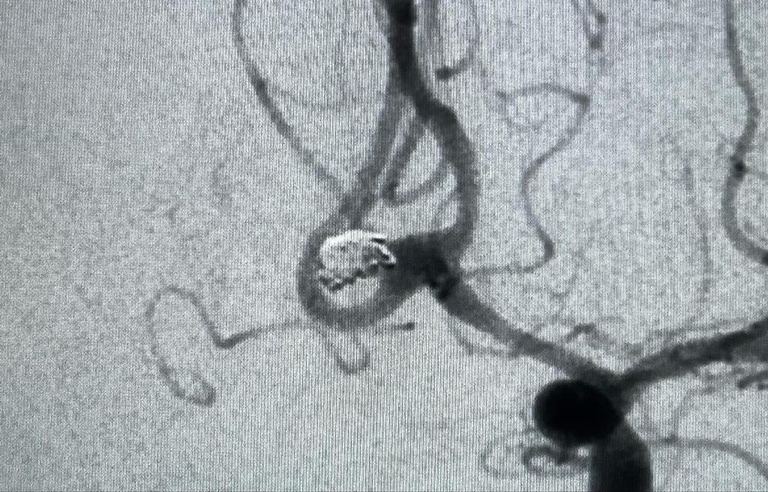

Huap realiza primeira embolização arterial para tratamento de aneurisma cerebral

Hospital é o único do SUS a realizar o procedimento na Região Metropolitana II do Rio de Janeiro

Embolização

Embolização 1

O Hospital Universitário Antônio Pedro (Huap-UFF), da Empresa Brasileira de Serviços Hospitalares (Ebserh), realizou, pela primeira vez, uma embolização arterial para o tratamento de aneurisma cerebral. O procedimento ocorreu no fim de 2022 e foi realizado na Radiologia do HU, pelo Serviço de Hemodinâmica. O projeto é pioneiro na Região Metropolitana II do Rio de Janeiro, sendo o Huap o único a ofertar aos pacientes uma tecnologia que antes não estava disponível.

A embolização no cérebro é importante ferramenta terapêutica e minimamente invasiva, já que não ocorre a abertura do crânio. Hoje, é possível fazer intervenções antes realizadas apenas através de cirurgia, permitindo ao paciente uma alta precoce. Segundo o coordenador do Serviço de Radiologia do Huap, Prof. Guilherme Abrão, os procedimentos endovasculares cerebrais são indicados no tratamento de aneurismas intracranianos, malformações vasculares intra e extracranianas, além de auxiliarem no tratamento de tumores do sistema nervoso e nas doenças vasculares da medula espinhal.

- O procedimento é realizado através da punção de uma artéria do corpo, geralmente na virilha. Através da injeção de contraste, o médico analisa em tempo real a circulação intracraniana e por cateteres. Ele é guiado pela imagem para, assim, realizar o tratamento de doenças arteriais e venosas intra e extracranianas. Atualmente, esses procedimentos são realizados, em larga escala, na abordagem terapêutica do Acidente Vascular Cerebral (AVC) isquêmico, que é a segunda principal causa de morte no mundo –, explica Guilherme.

O trabalho multidisciplinar, em conjunto com os Serviços de Neurocirurgia e Neurologia do Huap, tem o intuito de beneficiar muitos pacientes, já que as técnicas endovasculares não se limitam ao cérebro. “A Radiologia Intervencionista Oncológica está sendo estruturada, podendo, em breve, trazer benefícios aos usuários do SUS que estão inseridos no perfil da alta complexidade do hospital”, afirma Guilherme.